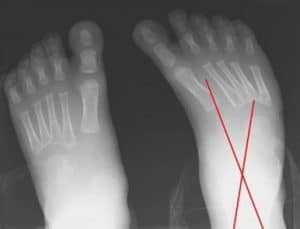

Figure 3: Dorsoplantar views obtained in a patient with unilateral clubfoot show that the talus and calcaneus are more overlapped than in the normal condition (Talocalcaneal angle is <15°)

Talocalcaneal parallelism is the radiographic feature of clubfoot (talipes). Simulated weight-bearing X-rays are used for infants who have not commenced walking. Positioning for foot x-rays is very important. The anteroposterior (AP) view is taken with the foot in 30° of plantarflexion and the tube at 30° from vertical. The lateral view is taken with the foot in 30° of plantarflexion. AP and lateral views can also be taken in full dorsiflexion and plantarflexion. This is especially essential in determining the total amount of dorsiflexion completed at the end of treatment, as well as the relative positions of the talus and calcaneum.

Measure the talocalcaneal angle in the AP and lateral films. AP lines are drawn through the center of the long axis of the talus (parallel to the medial border) and through the long axis of the calcaneum (parallel to the lateral border), and they usually subtend an angle of 25-40°. Any angle less than 20° is considered abnormal. The AP talocalcaneal lines are almost parallel in clubfeet. As the feet are correct with casting or surgery, the calcaneus rotates externally, and the talus reciprocally also derotates to a lesser degree to give a convergent talocalcaneal angle. Lateral lines are drawn through the midpoint of the head and body of the talus and along the bottom of the calcaneum, usually 35-50°. Clubfoot ranges between 35° and –10°.

The lateral talocalcaneal lines are almost parallel in clubfeet. As the feet are correct with casting or surgery, the calcaneum dorsiflexes relative to the talus to give a convergent talocalcaneal angle. These two angles, AP and lateral, are added to derive the talocalcaneal index, which in a corrected foot should be more than 40°. The AP and lateral talar lines normally pass through the center of the navicular and the first metatarsal.